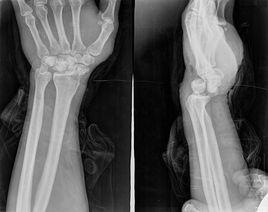

X線正位片顯示,脫位的月骨呈三角形(正常月骨應為四方形)。且投影與頭狀骨下端重疊。側位像顯示,月骨脫向掌側,半月形凹面也轉向掌側。